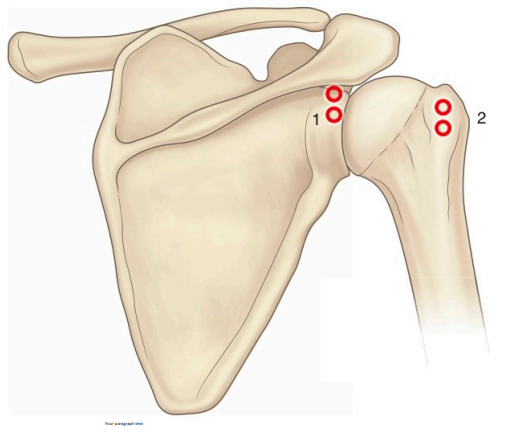

Shoulder joint

- RFA suprascapular nerve

- RFA shoulder joint